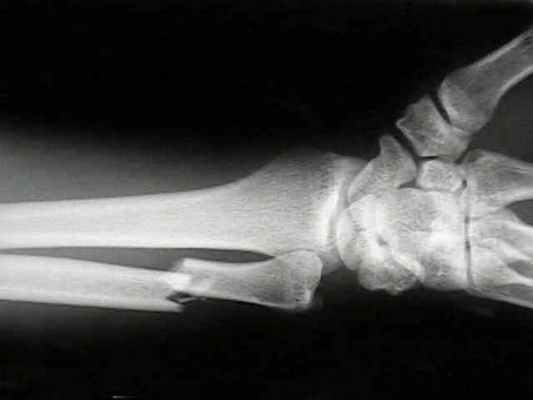

Перелом лучевой кости «в типичном месте» — перелом лучевой кости на 2–3 см проксимальнее суставной поверхности • Частота. 15–20% всех переломов. У пожилых женщин возникает в 2–3 раза чаще, чем у мужчин • Причины: падение на вытянутую руку с согнутой кистью • Патоморфология •• При падении на кисть в положении разгибания возникает разгибательный перелом Коллиса — дистальный отломок смещается в тыльную и лучевую сторону и супинирует, центральный смещается в ладонно-локтевую сторону •• При падении на кисть в положении ладонного сгибания возникает сгибательный перелом Смита — дистальный отломок смещается в ладонную сторону и пронирует, центральный — в тыльную сторону и супинирует • Клиническая картина: вилкообразная или штыкообразная деформация, при переломе Коллиса пальпируется на тыльной поверхности дистальный отломок, на ладонной — проксимальный, при переломе Смита дистальный отломок пальпируется на ладонной поверхности, проксимальный — на тыльной; резкая болезненность при пальпации лучевой кости и шиловидного отростка, осевой нагрузке. Часто повреждаются срединный нерв, межкостные ветви срединного и лучевого нервов (неврит Турнера) — резкие боли, парестезии, зоны анестезии, остеопороз костей кисти, ограничение движения IV пальца • Лечение •• Перелом без смещения — гипсовая лонгета (предплечье в среднем положении между супинацией и пронацией, кисть — лёгкое тыльное сгибание) на 3–4 нед •• Переломы со смещением — ручная или аппаратная репозиция, гипсовая повязка на 4–5 нед •• Неврит Турнера — витамины группы В, неостигмина метилсульфат, анаболические гормоны, тиреокальцитонин, прокаин внутрикостно.

• лучевой кости в типичном месте возникает вследствие падения на прямую руку с упором на ладонь. Немного реже такого рода перелом возникает при падении на тыльную часть ладони. Более распространены такие переломы среди людей, страдающих заболеваниями костей, снижающими их плотность. В большинстве случаев кость ломается на пару сантиметров выше лучезапястного сустава;